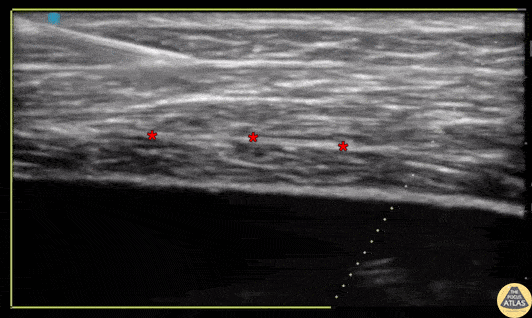

A transversus abdominis block is shown, with the needle approaching in plane, passing through the external oblique muscle superficially, then the internal oblique muscle in the middle, and depositing anesthetic in the fascial plane below the internal oblique muscle and superficial to the transversus abdominis muscle. This nerve block provides anesthesia of the hemi-abdomen and is useful in providing analgesia for conditions like appendicitis or diverticulitis. Dr. Nhu-Nguyen Le, Fellow Denver Health Ultrasound Fellowship